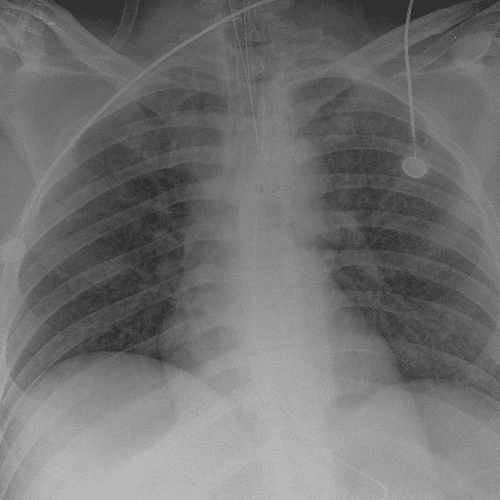

Practice Cases